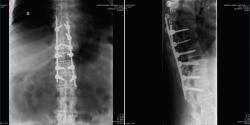

Después de realizar un control radiológico postoperatorio (Figura 6), inició la deambulación con ortesis semirrígida dorsolumbar en el postoperatorio inmediato. Mantuvimos la ortesis durante 2 meses, iniciando la rehabilitación con una evolución clínica excelente.

Figura 7. Control a los 2 meses de la cirugía.

Se realizó un control a los 2 meses de la cirugía, previo al inicio de rehabilitación (Figura 7).

En la Figura 8 vemos el control final a los 5 meses de la cirugía.